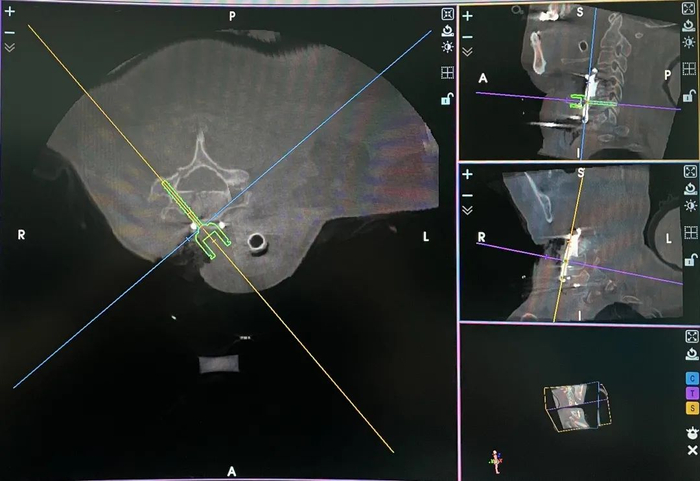

患者全麻后取仰卧位,使用Mayfield头架使头颈部固定确实,充分暴露术野后可见颈5椎体骨折碎裂严重,行颈4-5、颈5-6间盘切除,颈5椎体次全切除,将3D打印假体置入。应用骨科机器人完成颈椎前路椎弓根置钉规划,在机械臂辅助下,通过自主设计的导航套管针定位,于3D打印假体钢板钉孔内置入双侧颈4、颈6及颈7六枚前路椎弓根螺钉导针,O型臂X射线机验证导针路径精确无误,根据导针置入长度合适的椎弓根螺钉,6枚ACPS长度范围26mm-32mm。术中验证6枚螺钉均位于椎弓根内,与术前设计的理想钉道完全相符。

颈4、6、7六枚前路椎弓根螺钉置入术中影像